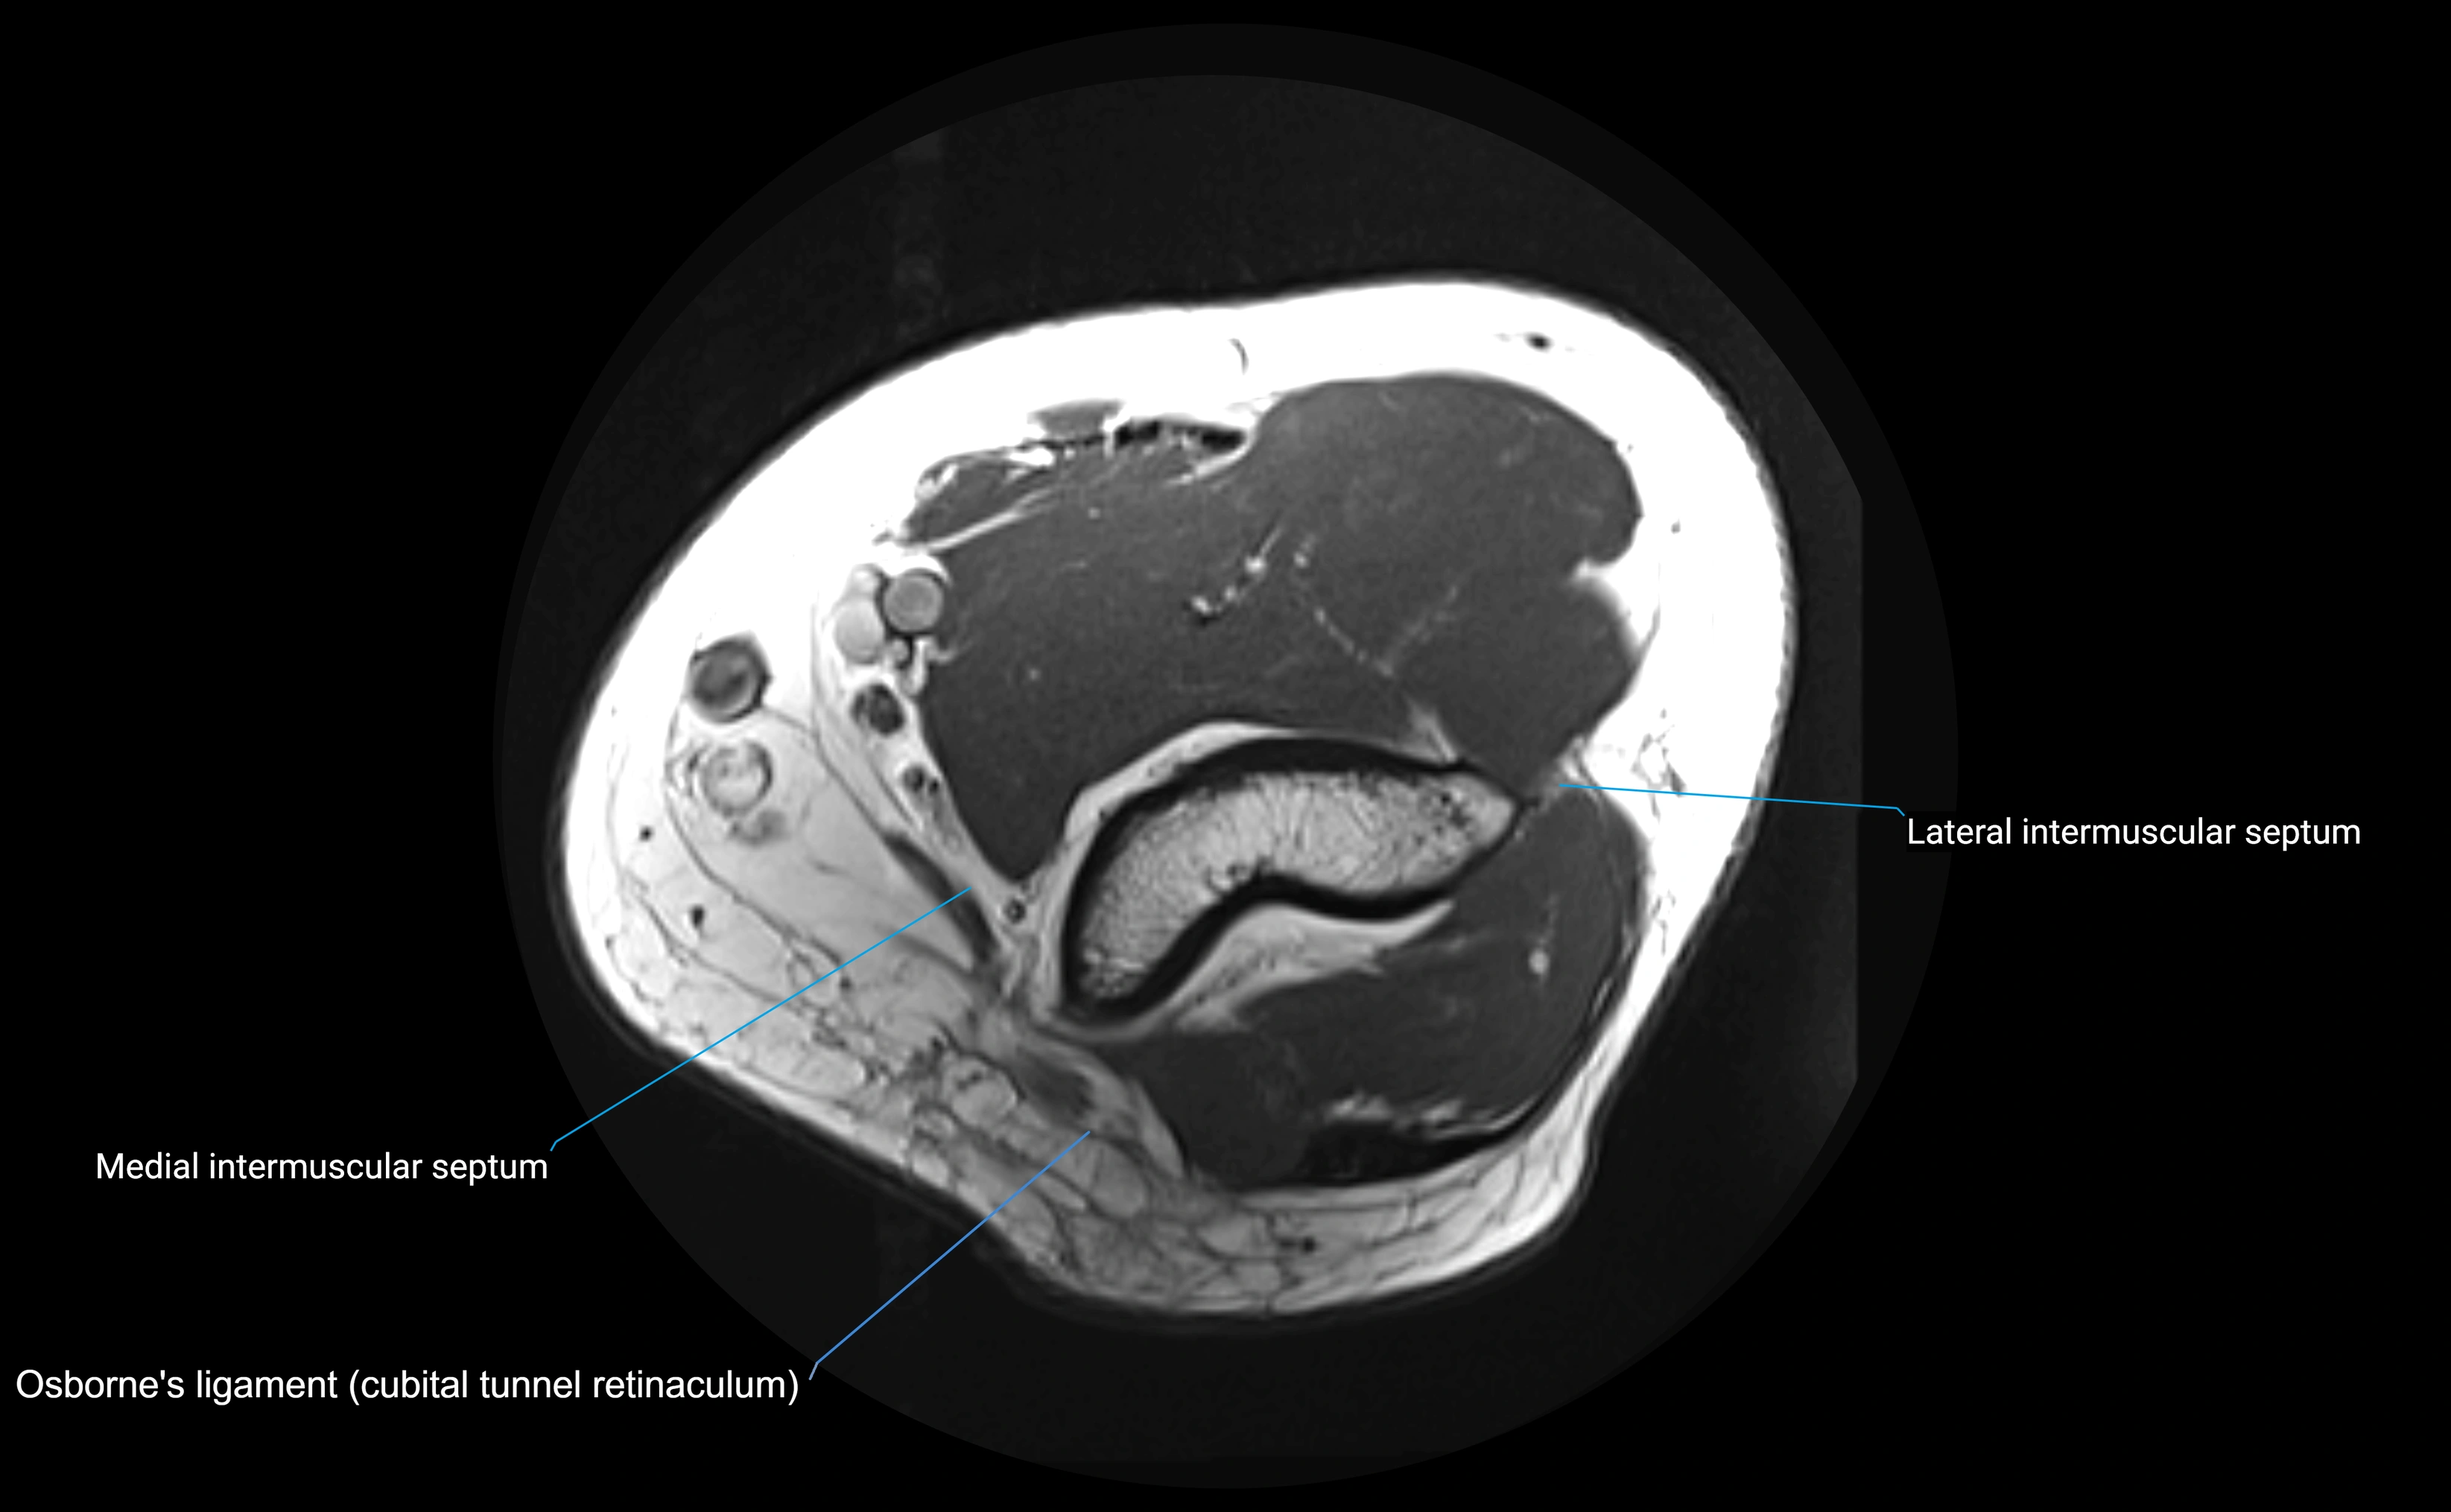

MRI Appearance

T1-weighted images:

• Ligament: low signal intensity (dark), appearing as a continuous band around the radial head.

• Adjacent fat and marrow: bright, creating contrast with the ligament.

• Thickening or disruption indicates injury or fibrosis.

• Joint capsule and synovium seen as thin low-signal lines contiguous with ligament margins.

T2-weighted images:

• Ligament: low signal (dark) with clear delineation from joint fluid.

• Fluid or edema: bright hyperintense, separating or surrounding the ligament in partial tears.

• Complete tear: discontinuity or non-visualization of ligament fibers, often with joint effusion.

STIR:

• Normal ligament: dark band encircling radial head.

• Pathology: bright hyperintense periligamentous signal suggesting edema, sprain, or partial tear.

Proton Density Fat-Saturated (PD FS):

• Normal: dark, well-defined band outlining the radial head.

• Partial tear: irregular or bright hyperintense signal within or adjacent to ligament fibers.

• Joint effusion and reactive synovitis appear bright and are well visualized.

T1 Fat-Sat Post-Contrast:

• Normal: minimal enhancement.

• Inflamed or injured ligament: focal or diffuse enhancement.

• Synovial enhancement in chronic instability or post-surgical changes.